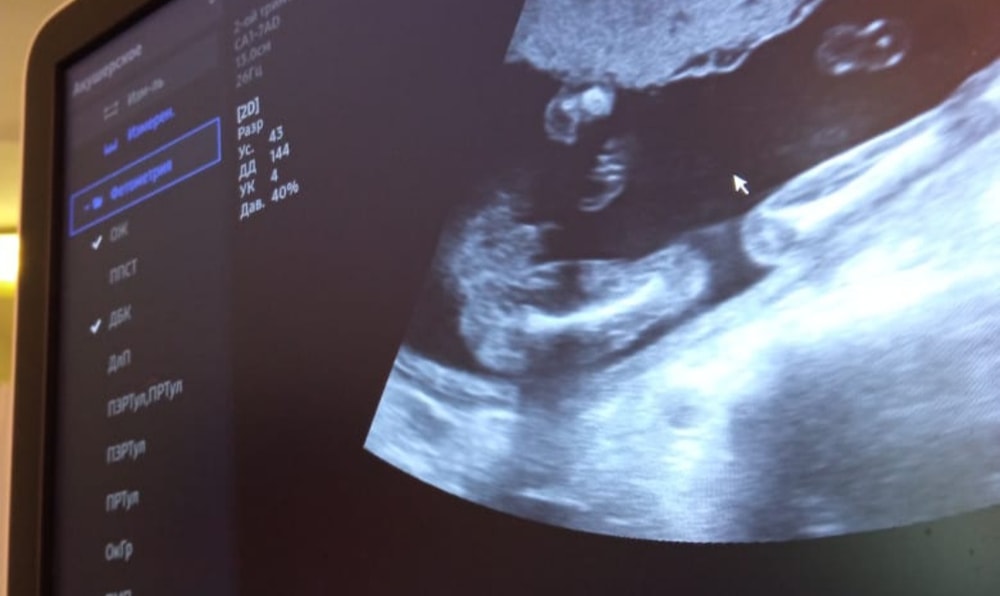

Пол малышаДевочки, на первом скрининге и потом в 16, 4 сказали что девочка, а сегодня была на цервикометрии и похоже у нас новые обстоятельства отросли)))) я переспросила еще не может ли это быть пуповина, врач сказала, что пуповина бы кровоток показывала, а тут нет… я уже настроилась на девочку)))))

У меня в 15 недель тоже предположили девочку, в 18 недель и далее - тоже выросли обстоятельства)))

Как и у вас. Очевидно все. Мальчик)